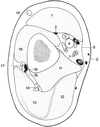

Coupe axiale de l’articulation gléno-humérale

- Espace entre clavicule et 1ere côte

- M. grand pectoral

- M. petit pectoral

- V. axillaire

- A. axillaire

- Faisceaux médian

- Faisceau postérieur

- Vaisseaux thoraciques latéraux

- M. dentelé antérieur

- Syssarcose serrato-thoracique

- M. sub-scapulaire

- M. infra- épineux

- Surface articulaire glénoïdale

- Bourrelet glénoïdale

- Partie inf de la tête humérale

- M. deltoïde

- Faisceaux latéral

- Nerf musculo-cutané

- Tendon commun du coraco-brachial et de la portion courte du biceps brachial

- Tubercule mineur de l’humérus

- Tubercule majeur de l’humérus

- Tendon du chef long du muscle biceps brachial